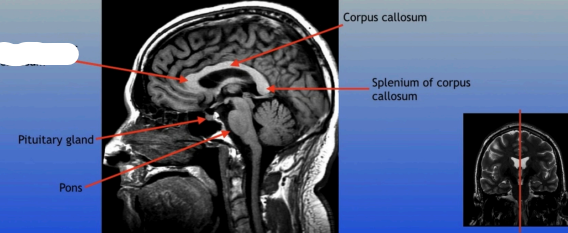

Pituitary Gland

A small pea-sized gland located at the base of the brain, often referred to as the "master gland" because it regulates many bodily functions through hormone secretion.

Pons

A round structure located above the medulla oblongata and below the midbrain, it acts as a relay station for signals between the cerebellum and cerebrum, and plays a role in regulating sleep and arousal.

Corpus Callosum

Splenium of Corpus Callosum